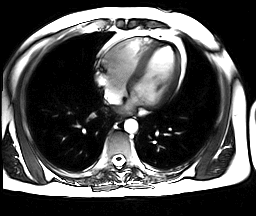

Сердце – орган средостения, который отвечает за перекачивание крови и является одним из самых значимых в организме человека, поэтому очень важно заботится о его здоровье. Магнитно-резонансная томография позволяет выяснить, в каком состоянии находится этот орган, его клапаны и коронарные сосуды.

Преимущества МРТ в кардиологии:

- высокая контрастность при сканировании мягких тканей (т.е. сердца);

- возможность сканирования в интересующей плоскости;

- отсутствие инвазивности;

- из-за наличия естественного контраста от движущейся крови возможна оценка особенностей гемодинамики без применения контрастирующего вещества;

- возможность построения трехмерного изображения органа для изучения особенностей кровоснабжения, выявления стенозов в коронарных сосудах и очагов кровоизлияния.